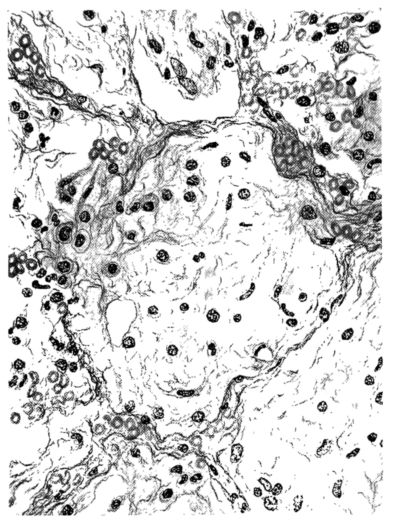

The changes are less marked, perhaps, in the trachea than in its finer ramifications. The mucosa is constantly more or less destroyed and large areas, usually focal, are entirely devoid of their epithelial covering. This is replaced by a sparse exudate, composed largely of red blood cells, mucus, a small amount of fibrin, and nuclear fragments (Fig. II). It may dip into the submucosa for a short distance, but usually these indentures are associated with the ducts of the mucous glands into which the inflammatory reaction extends. A more striking feature than the exudate, however, is the edema and the congestion of the submucosa. The loose areolar tissue of the submucosa is spread widely apart, and throughout it distended blood vessels are very conspicuous. Occasionally such a vessel is broken and actual hemorrhage appears in the submucosa. Occasionally, too, the inflammation extends down the duct to the mucous gland itself, and here, also, aplastic inflammatory reaction is evident, inasmuch as the acini now stain intensely red with the cells undifferentiated from each other and specked here and there by broken remains of the dead nuclei (Fig. III). After the disease has continued for a short period, even at the end of five or six days, some regeneration of the epithelial lining may be seen (3) (Fig. IV). But despite this, the acute picture persists, and there goes on, side by side, an attempted repair characterized by epithelial regeneration and the same evidence of acute change. Since the lesion is essentially a superficial one, scars or contractures of any extent are not encountered in the trachea, even in examples of the disease that have ended fatally only after many weeks.[4]

FIG. VIII. AUTOPSY NO. 97. ALTHOUGH THE EPITHELIUM IS STILL VISIBLE AS A HYALINE BAND LIFTED FROM THE UNDERLYING MUCOSA, BOTH MUCOSA AND SUBMUCOSA ARE INVOLVED IN A NECROTIZING PROCESS. BACTERIA ARE ABUNDANT IN THE DEAD TISSUE.

15There is considerable evidence to support the view that the disease spreads from bronchus to bronchus, and in keeping with this view, various stages in the inflammatory processes are more readily determined in these smaller structures than in the trachea. Furthermore, it must be emphasized that even the mildest and the most extreme of these stages are not infrequently encountered in the same lung. The earliest lesion is manifested by an increased homogeneity of the protoplasm of the epithelial lining of the bronchus. The cell protoplasm loses its normal granulation and the nucleus, somewhat darker than usual, becomes conspicuous on a red base (Fig. V). In the lumen of such a tube a serous exudate, perhaps mixed with mucus, is encountered, and there is some spreading apart of the surrounding muscular tissue with engorgement of the vessels. This picture merges gradually into one where the epithelium appears as a homogeneous, red-staining ribbon, devoid of nuclei, often exfoliated, in part at least, from the underlying submucosa (92). The change is traceable through the larger bronchi, even to the ducti alveolares, and not infrequently, bacteria, either as a diffuse, minute dotting or in the form of circumscribed, colony-like formations, are spread through the red, ribbon-like strand (Fig. XVI). With the exfoliation of the epithelial lining, the submucous vessels become more and more conspicuous and may bulge into the lumen of the tube (Fig. VI). That they actually weep into the lumen is proved by the presence of red blood cells in the exudate, now rich in mucus, broken-down nuclei, and desquamated cells. The necrotizing process may not extend deeper than the epithelial lining as is the status described above (140, 162), but it also frequently involves the underlying submucous and muscular layers, so that these lose their identity and stand out as homogeneous masses, in which fragmented nuclei and bacterial accumulations are prominent. Such deeper necrotizing areas may be focal (Fig. VII), or may involve the entire circumference of the tube (Fig. VIII). Occasionally, the epithelium, now dead and staining homogeneously, is lifted from the underlying submucosa in the form of a blister (66), and has very much the same appearance as the well known, early reaction which follows the application of croton oil to the rabbit’s ear. Where this occurs, the submucosa is less involved, as though the necrotizing agent had not penetrated to the same depth and the serous reaction beneath were actually a beneficent exudate. These blisters are in contrast with the deeper areas where the fibrinous mass, mixed with the dead tissue, forms an intensely staining ring or band, which extends through the bronchiolar wall even to the surrounding alveoli.

In the early stage of this process one of the most outstanding features is the absence of polynuclear leucocytes in the reactionary process, but gradually as the dead tissue sloughs away, these cells wander into the exudate and form a purulent ring, more intense in the lumen, but extending for a variable distance through the still viable wall of the structure (47) (Fig. IX). Later mononuclear cells accumulate in this wall and occur either as a diffuse mottling or as circumscribed foci in the muscle and submucous layer of the bronchiole, just as they do in the trachea. Occasionally, a striking change is found in a small bronchiole within a portion of the lung which is otherwise uninvolved by an inflammatory process. Perhaps the alveoli were the seat of a change which has subsided, but, whatever the history, the purulent mass in the bronchiole and involving its wall, stands out effectively (Fig. X).